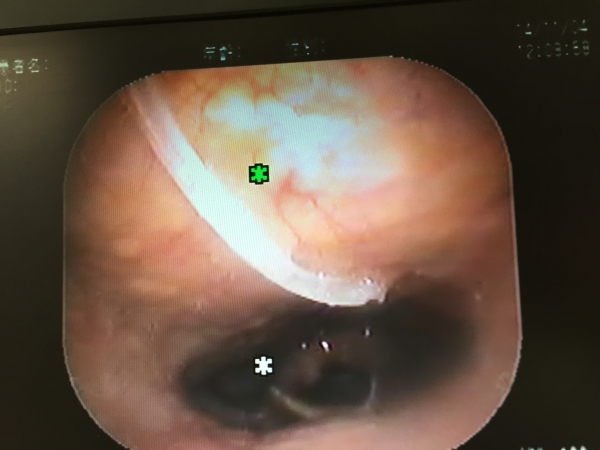

直視では見えず、喉頭鏡を覗いた主治医は「コリャ、太か骨ねぇ〜!!ナンバ喰うたらこぎゃん骨が喉に突きササッとですか?!」と小生に尋ねられたんですが小生の鼻は喉頭鏡で塞がれておりますのでまともに話す事はできません。。。 でっ、結局、局所麻酔下の下、喉頭鏡を用いた異物(=魚:イサキの骨w)除去術を敢行したのでありました。。。

口から飲み込んだイサキの骨は小生の右鼻から出てきましたがイサキの骨は小生の喉に20mm「ぬかって」おりました。。。 主治医が看護師に「鉗子ば緩めたらイカンケンね!!放すなよ!!」と恐ろしい事を言っておられた事は聞き逃しませんでした。。。泣

写真は除去できましたイサキの骨と大きな骨に見入られた耳鼻科の主治医がデジカメで「イサキの骨!!」を写メしているお姿を写メ返ししている模様と喉頭鏡で小生の喉にイサキの骨が突き刺さっている様子であります。。。